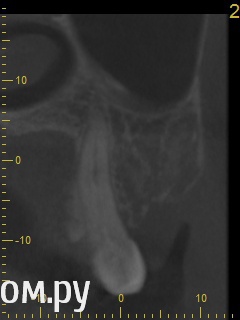

red_butler Опубликовано 21 апреля, 2014 Поделиться Опубликовано 21 апреля, 2014 Снимок во время лечения делали? Коффердам и оптика использовались? На кт в тех срезах что Вы выложили кисты не вижу Ссылка на комментарий

Гарриевич Опубликовано 21 апреля, 2014 Поделиться Опубликовано 21 апреля, 2014 Кисты по снимкам нет. Удалять зуб ,по снимкам, причин нет Ссылка на комментарий

DmitrySH Опубликовано 21 апреля, 2014 Поделиться Опубликовано 21 апреля, 2014 Аналогично, никаких признаков воспаления в костной ткани вокруг зуба не увидел. Ссылка на комментарий

igorstom Опубликовано 26 апреля, 2014 Поделиться Опубликовано 26 апреля, 2014 (изменено) Понятие кисты двоякое. Кистой можно назвать полостное образование размером на рентгеновском снимке более 8 мм в диаметре. Ну а есть понятие гистологическое. Тут размер не имеет значения. А результаты гистологического исследования - эпителиальная выстилка и клеточные элементы. В практике, по крайней мере у нас на Урале доктора часто "кистами" называют даже незначительные округлые элементы на верхушках корней. Так что причин на мой взгляд для беспокойства нет. А вот пустота каналов лично меня насторожила бы. Гидроокись кальция всё-таки рентгеноконтрастна, хоть и незначительно. Но и этого я не увидел на снимках. Но это только моё вИдение. Изменено 26 апреля, 2014 пользователем igorstom 1 Ссылка на комментарий